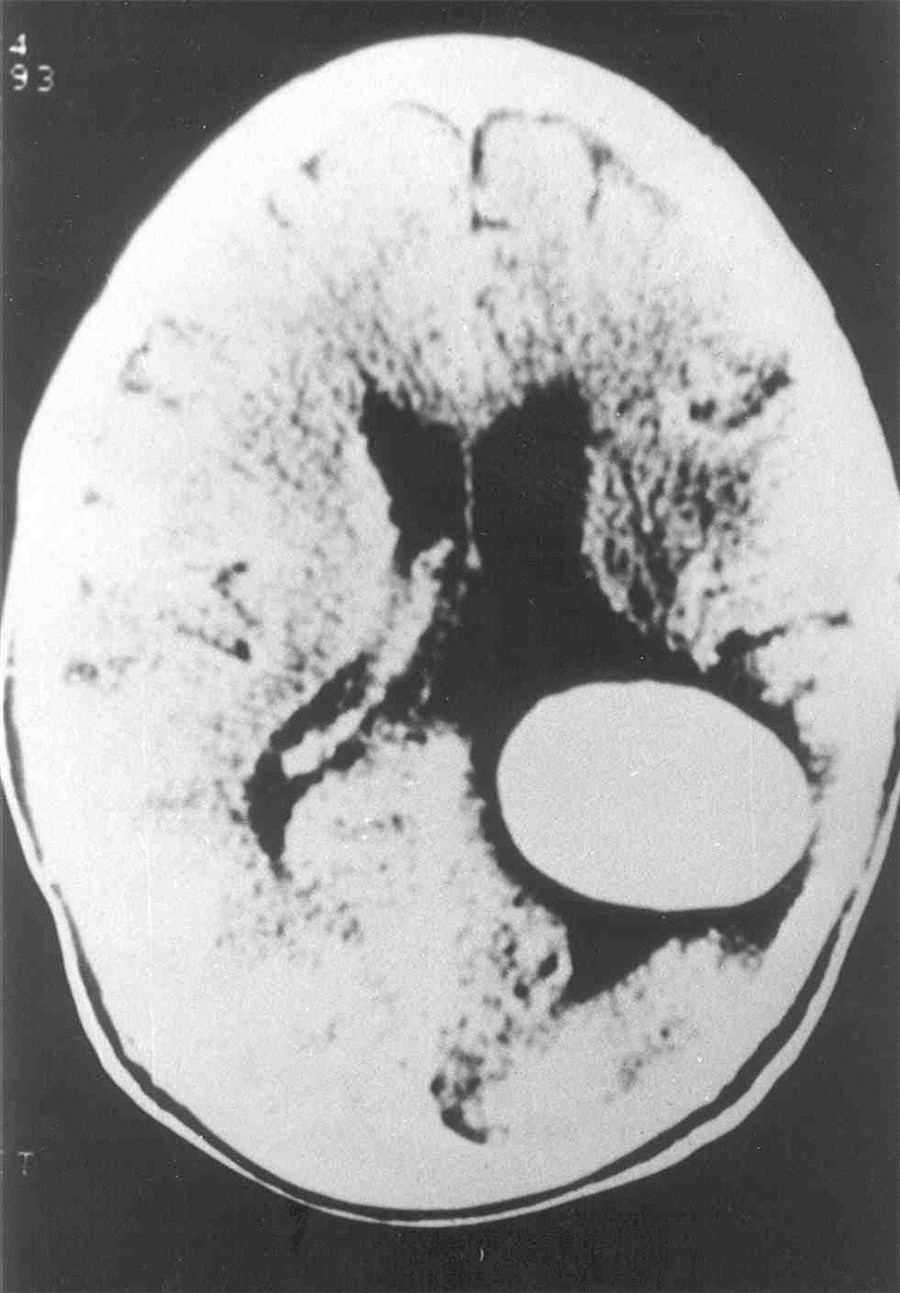

Gliomas

Gliomas are brain tumors that arise from the supporting cells of the brain (‘glia’). These can be diffuse, involving large area of the brain or may be localized. They can be low grade (benign behavior), or high grade (malignant). They often present with headache, neurological weakness, etc and require early surgery for diagnosis, reduction of tumor mass, often followed by radiotherapy and chemotherapy.